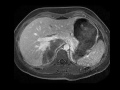

Retroperitoneal neurofibroma

MRI images demonstrate an unusual mass in the right suprarenal fossa which is T1 and T2 hypointense with very little enhancement. This was found to be a retroperitoneal neurofibroma at surgical resection.